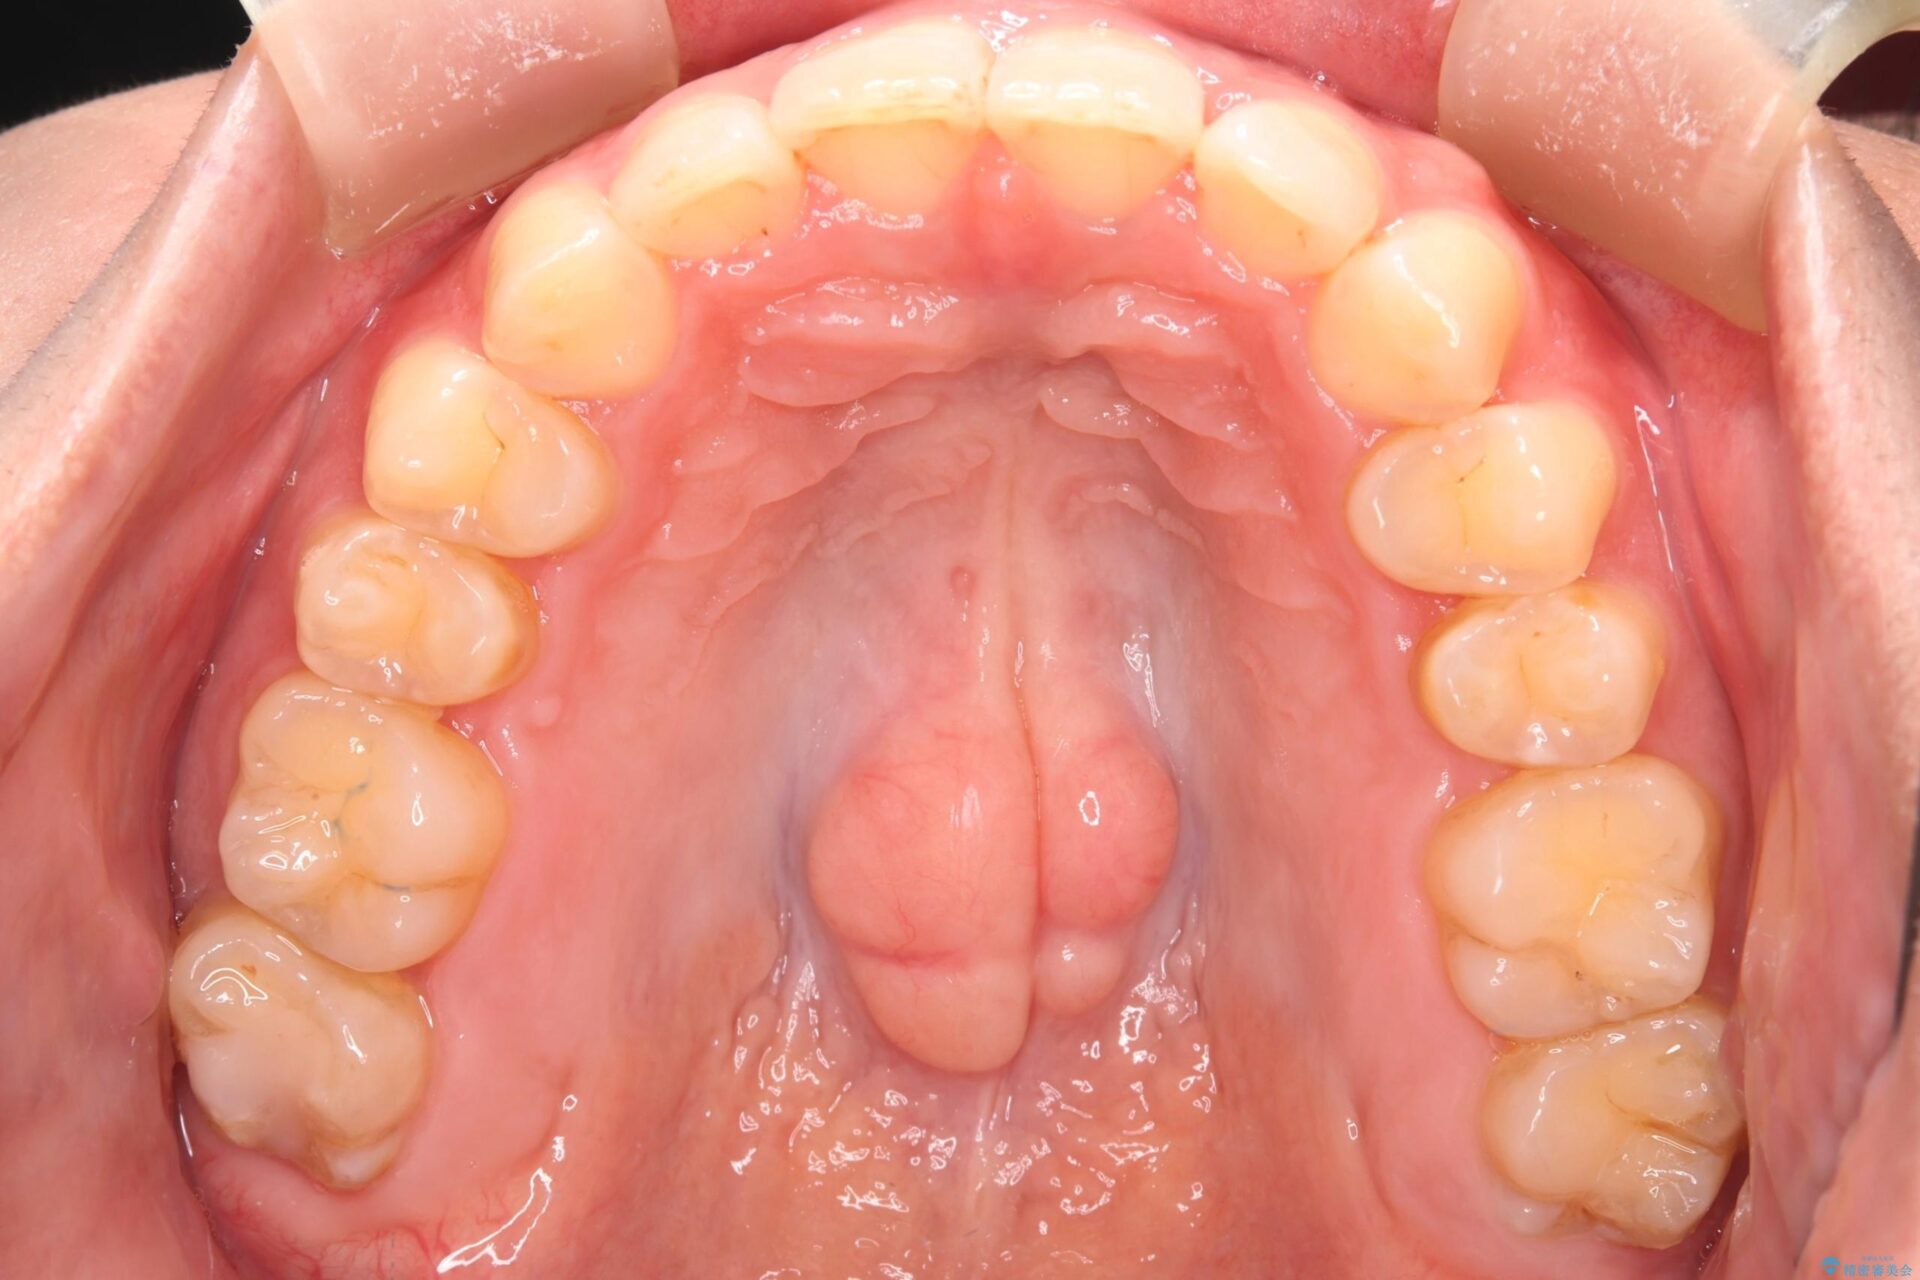

下の歯のガタつきが気になるとご来院された患者様です。

下の歯のがたつきと右の奥歯の噛みあわせ改善する治療計画を立てました。

まず右側臼歯部の咬合改善のために、臼歯部のみ部分的なワイヤー矯正を行い、咬合改善がみられてからインビザラインにて全体的な矯正を行なっていくこととします。